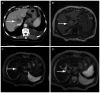

Figure 1.

Imaging examination in the representative case of a 73-year-old patient diagnosed with hepatocellular carcinoma. The tumor was successfully detected with DWIBS/T2. (A) CECT scanning demonstrated a space-occupying lesion with mixed enhancement (arrow). (B) T1WI showed an unclear mass-like lesion. (C) Detection of the lesion was difficult in a T2WI when compared with the CECT scan. (D) DWIBS/T2 clearly showed a high signal. DWIBS/T2, diffusion-weighted whole-body imaging with background body signal suppression/T2-weighted image fusion; CECT, contrast-enhanced computed tomography; WI, weighted image.